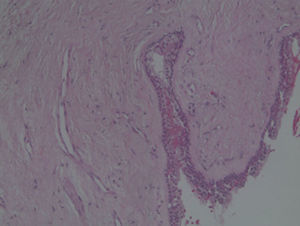

Case reportA case of a nasopalatine duct cyst in a 45-year-old male is presented (Fig. 1). The patient was referred, reporting a pressure over the anterior maxilla. There were no other symptoms and no recent history of pain. Clinical examination revealed a palatal expansion on the anterior hard palate (Fig. 2). There was no previous history of trauma. The patient was asked to take a computerized axial tomography which showed a well-defined radiolucency in the anterior maxilla in the region of incisive canal (Fig. 3). Loss of cortical bone was seen along the palatal aspect of the lesion in the sagittal sections (Fig. 4). Also resorption of nasal cavity floor bone could be seen in those sections. The cyst was enucleated under general anaesthesia. A palatal mucoperiosteal flap was raised and following bone removal, the friable, haemorrhagic cyst lining was curetted and sent for histological examination fixed in 10% neutral formalin (Figs. 5 and 6). After cyst removal it could be seen in the depth of surgical loca a small communication with the nasal cavity. Gross examination revealed a whitish, soft consistency fragment measuring 2.2cm×1.5cm×0.4cm (Fig. 7). Microscopic examination revealed fibrous wall lined by thin stratified squamous epithelium without inflammatory infiltrate and with some clear cells of ciliated appearance, which confirms the diagnosis of nasopalatine duct cyst (Fig. 8). The patient showed no clinical or radiographic signs of recurrence one year after surgical excision (Fig. 9).

NPDC may be delined by a variety of different types of epithelium that ranges from stratified squamous to pseudostratified columnar, or a combination of these.4,7,10 In this case we found both respiratory and squamous type of epithelial cells. Respiratory epithelium is seen only in 9.8% of the cases.14 The connective tissue wall contains small arteries and nerves, representing the nasopalatine neurovascular bundle. Collections of mucous glands and scattered chronic inflammatory cell infiltrate are frequently present.6,7,10